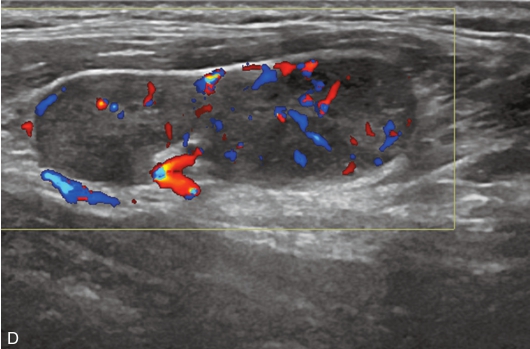

甲状腺左叶上极及下极分别可见一个低回声,大小约为0.8cm×0.9cm×0.6cm,边缘模糊,纵横比>1,内可见多发点状强回声;CDFI示结节内均未见明显血流信号。双侧颈部可见多发肿大淋巴结,其中左侧Ⅲ区可见一个大小为2.2cm×0.8cm、形态规则、淋巴门回声偏心、皮质回声增厚的结节;CDFI示淋巴结内可见丰富血流信号,见图1-9-3。

图1-9-3 甲状腺髓样癌及颈部淋巴结常规超声图像

A.甲状腺左叶上极低回声结节灰阶超声图像;B.CDFI示未见明显血流信号;C.左侧Ⅲ区结节灰阶超声图像;D.CDFI示结节内可见丰富血流信号

甲状腺髓样癌超声造影图像,见图1-9-4、ER1-9-2。

图1-9-4 甲状腺髓样癌超声造影图

A.动脉早期;B.达峰时;C.增强晚期

视频注解:甲状腺左叶上极及下极病灶超声造影表现为增强晚于周围甲状腺组织,达峰时呈不均匀低增强

甲状腺髓样癌结节增强开始时间晚于周围组织,由周边向中心灌注,呈“向心性”增强,达峰时呈不均匀低增强。

结节内造影剂晚于周围甲状腺组织,先于结节周边部分增强,而后达到中央区,呈“向心性”强化特点,达峰时呈不均匀低增强。与甲状腺髓样癌超声造影鉴别困难,需结合实验室检查。